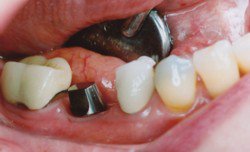

• دوم يعني دندانپزشک فيکسچر را در استخوان فک قرار داده است و بعد از گذشت دو الي سه ماه، قطعه دوم ايمپلنت را که هيلينگ نام دارد روي فيکسچر بسته تا در اطراف آن لثه شکل بگيرد. سپس قطعه سوم (اباتمنت) به همراه دندان چيني (ساخته شده توسط دندان ساز) که تکميل کننده ايمپلنت مي باشد، به جاي هيلينگ قرار مي گيرد. دندانپزشک دندان چيني را روي اباتمنت مي چسباند. در اين زمان بيمار مي تواند همانند دندان طبيعي از دندان مصنوعي خود استفاده کند.

ايمپلنت دنداني براي جايگزين کردن يک يا چندين دندان از دست رفته کاربرد دارد و مي تواند براي تمام دندان ها به صورت ثابت يا متحرک استفاده شود. در هر دو حالت فوق کلمه ايمپلنت استفاده مي شود اما حالت دوم بيانگر معني واقعي ايمپلنت مي باشد و به مجموعه اي از قطعات ايمپلنت گفته مي شود و هر کدام از قطعات به تنهايي نام و کارايي مجزايي دارند که در قسمت نحوه کاشت ايمپلنت، توضيح جامعي را براي تمامي مراحل آن از زمان گرفتن نسخه براي راديوگرافي تا چسباندن دندان چيني ارائه مي دهيم. ايمپلنت از نظر ظاهري مشابه دندان طبيعي است و در دهان همان حس طبيعي را براي جويدن القا مي کند و سوء هاضمه ايجاد شده بر اثر ناتواني در جويدن غذا را برطرف مي کند.